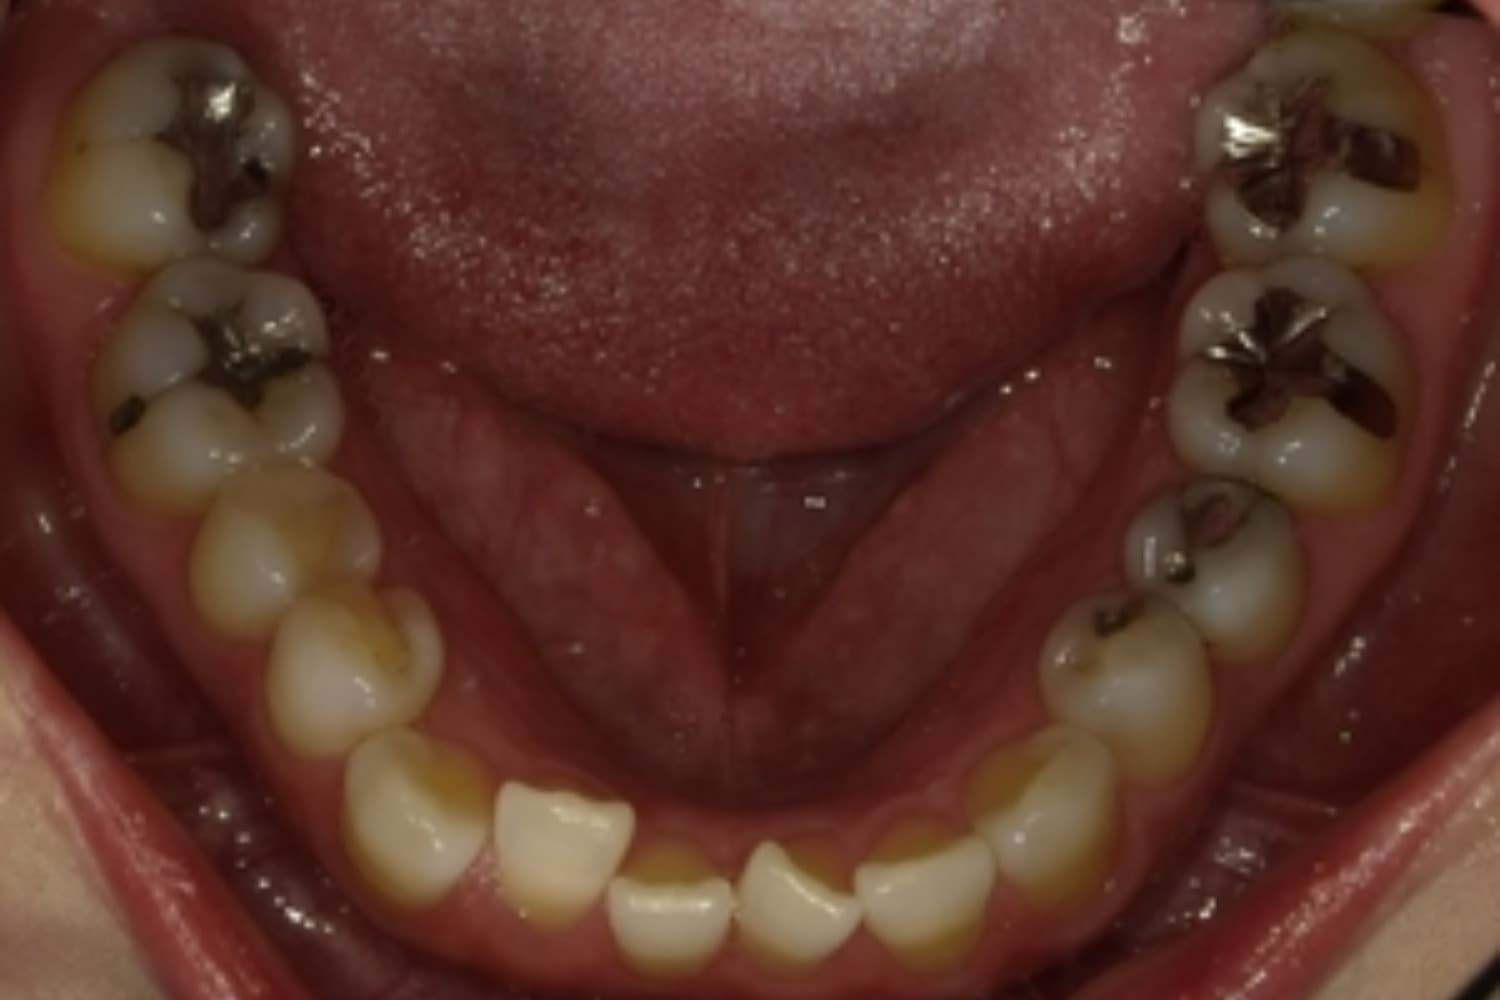

ガタガタとした歯並びや八重歯(1)

Before

After

ガタガタとした歯並びや八重歯をマウスピース矯正(インビザライン)にて治療

主訴

下の前歯のガタガタが気になる

治療期間

2年5カ月

費用

90万円